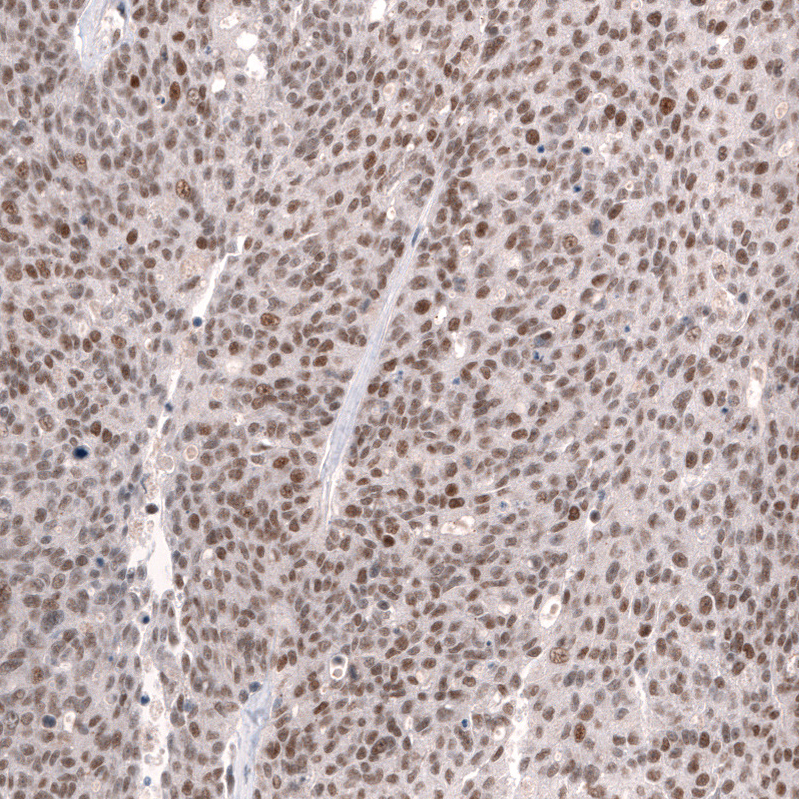

Immunohistochemical staining of human cerebral cortex shows strong nuclear positivity in neurons.